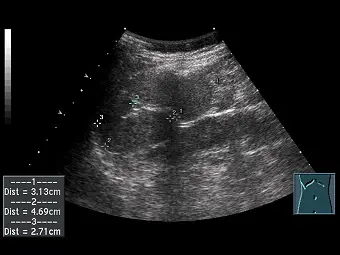

有一疑似異位綜合症( heterotaxy syndrome )之患者,超音波掃描時在左上腹部找不到正常脾臟,反而在右上腹發現多個橢圓形軟組織(如下圖所示),最有可能的診斷為何?

- 影像掃描切面:根據超音波影像右下角的體表標記 (body mark),探頭位於患者的右上腹 (Right upper quadrant, RUQ) 肋骨下緣。

- 超音波特徵:影像中可見多個邊界清晰、呈橢圓形的均質軟組織腫塊,其回音性 (echogenicity) 與正常脾臟實質相似。圖中標示了三個主要的結節,測量大小分別為 3.13 cm、4.69 cm 及 2.71 cm。

- 臨床意義:在左上腹找不到正常脾臟,反而於右上腹發現多個